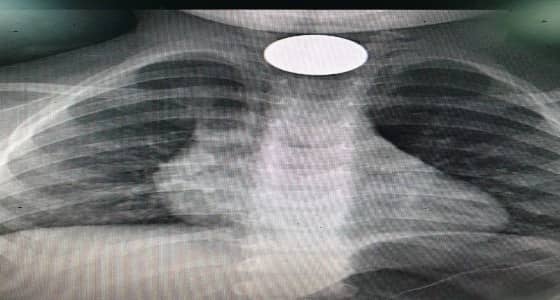

تمكن فريق طبي بمستشفى جنوب القنفذة، الخميس الماضي، من استخراج قطعة معدنية من أعلى مريء طفل يبلغ من العمر قرابة سنتين ونصف باستخدام المنظار.

ومن جانبه، قال استشاري الأنف والأذن والحنجرة وجراحة الرأس والعنق، الدكتور علي القوزي، على لسان المتحدث الرسمي لـ " صحة القنفذة " إبراهيم المتحمي، أن الطفل قدِم لطوارئ المستشفى وهو يشتكي من بلع جسم غريب " قطعة نقود معدنية" كانت قد عَلِقت في أعلى المريء.

وأوضح " القوزي " أن ذلك تَسَبّب في اختناق وعدم القدرة على البلع؛ عندها قرر الفريق الطبي إجراء عملية منظار صلب للمريء، واتضح أنها قطعة معدنية نقدية فئة الربع ريال؛ فيما نجحت العملية التي استمرت ١٠ دقائق فقط ودون حدوث مضاعفات؛ حيث غادر الطفل المستشفى وهو بصحة جيدة.